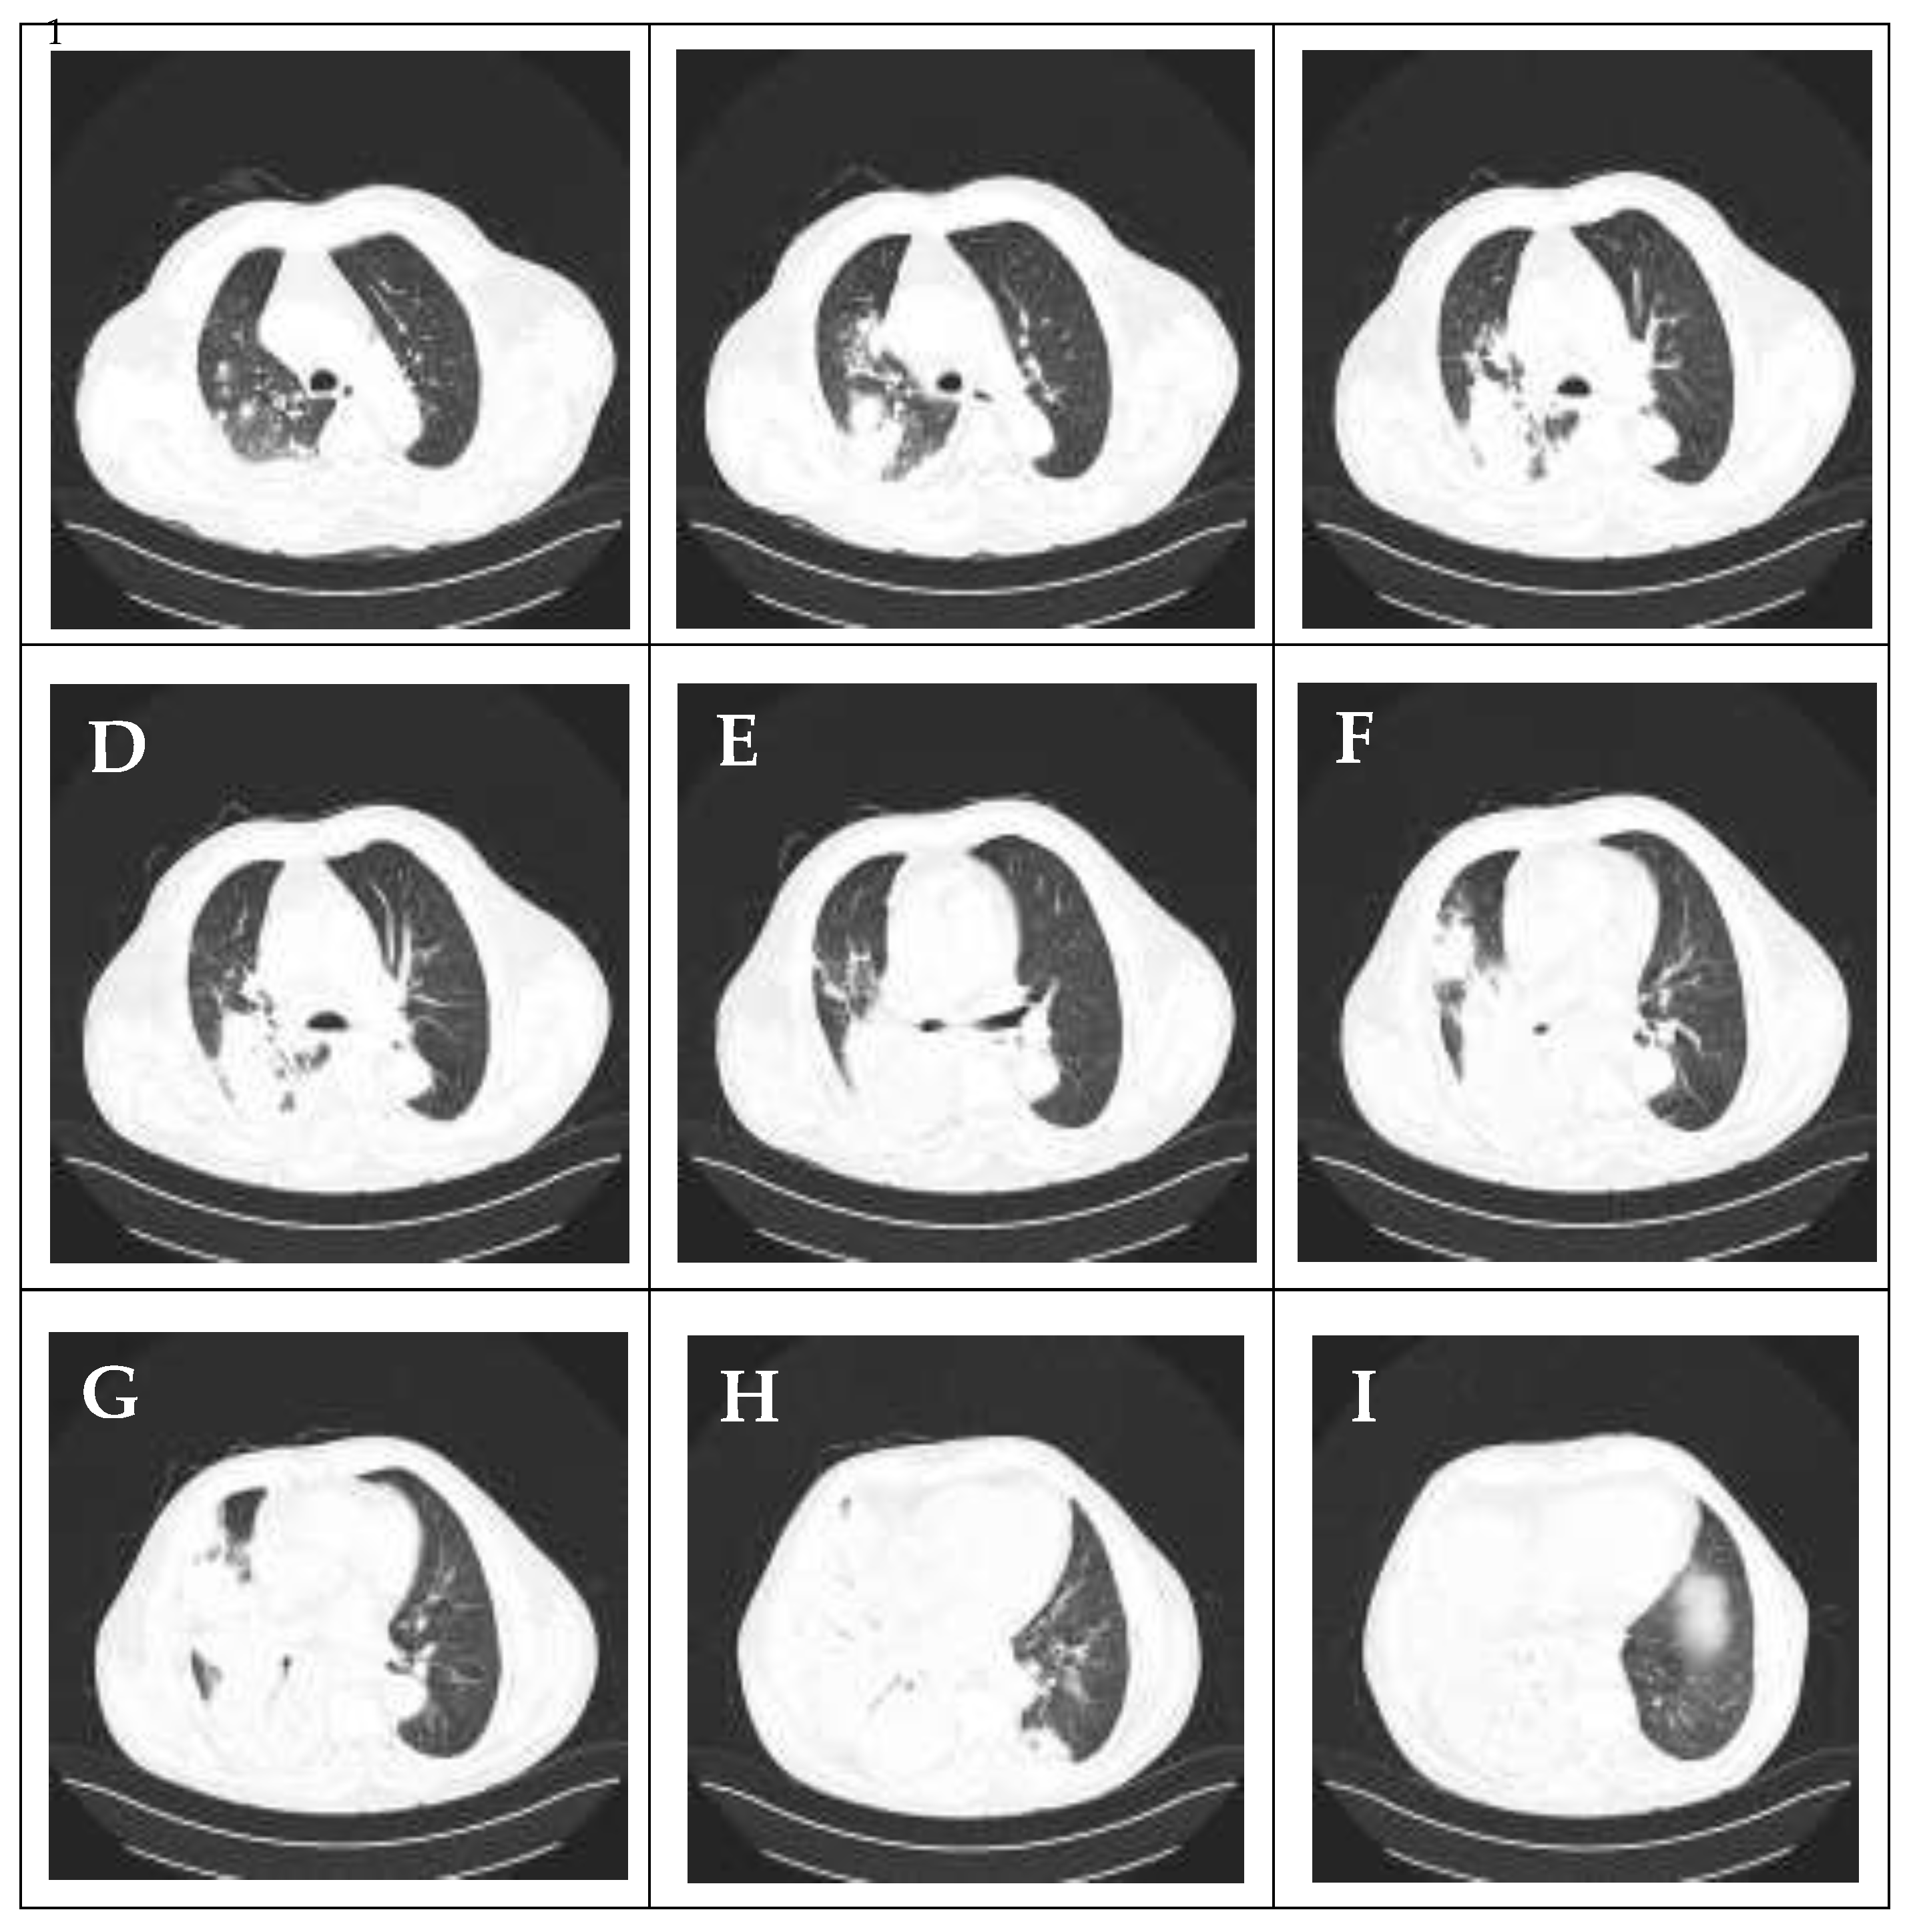

Computed tomography (CT) of the thorax, performed on admission, confirmed the diagnosis of right lower lobe pneumonia with involvement of small areas in the right upper lobe. Furthermore, the CT revealed an air bronchogram, a “tree-in-bud” sign, a small area of inflammation in the left lower lobe, and a small right-sided pleural effusion (less than 20 mm) not indicated for drainage (Figure 2).

Figure 2. CT images of the chest obtained on admission demonstrate lobar pneumonia predominantly affecting the right lung. The scan reveals: (A–C) multiple inflammatory foci in the right upper/middle lobe; (D–I) dense consolidation with air bronchograms in the right lower lobe, alongside with smaller foci of inflammation in the left lower lobe; and a small associated right-sided pleural effusion.